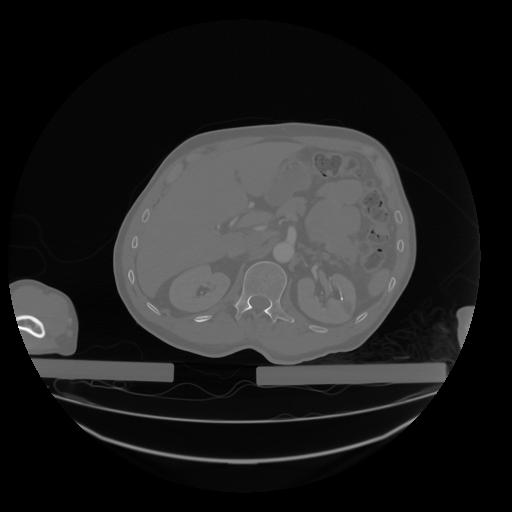

28 CUERPO,CE,Vol,2.0,CUERPO,,